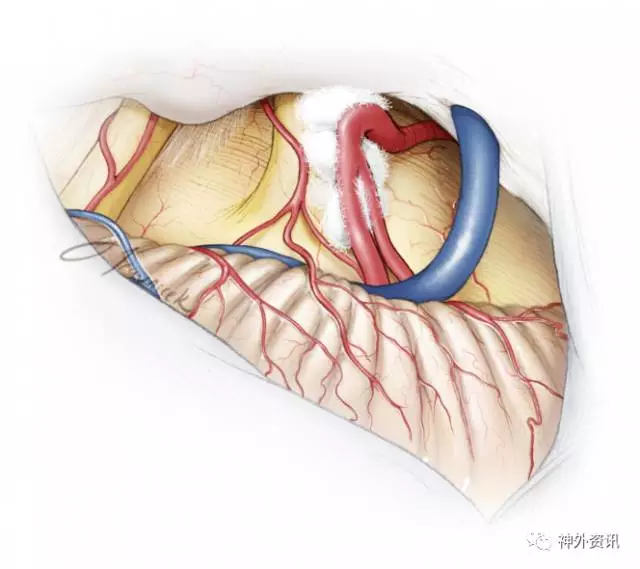

图12. 笔者特意在三叉神经肩部及腋内侧塞入一块teflon棉垫,防止血管与REZ区或脑干之间的任何接触。

图13. 最后的结果是将动脉全程隔开,使血管使其远离神经,避免与神经组织有任何接触。可以用纤维蛋白胶用来加固这种结构。要避免使用过多Teflon棉,防止肉芽肿形成,这可能导致疼痛复发。

中央髓鞘沿着三叉神经延伸至远侧,到达Meckel腔。因此减压术应尽可能完整覆盖神经全长。岩骨上任何阻碍术者视野的骨隆起都应被磨除,直至可以探查到神经全长。沿着神经的所有血管都应被游离:动脉以及大静脉应被游离且垫上棉垫,小静脉直接电凝切断。